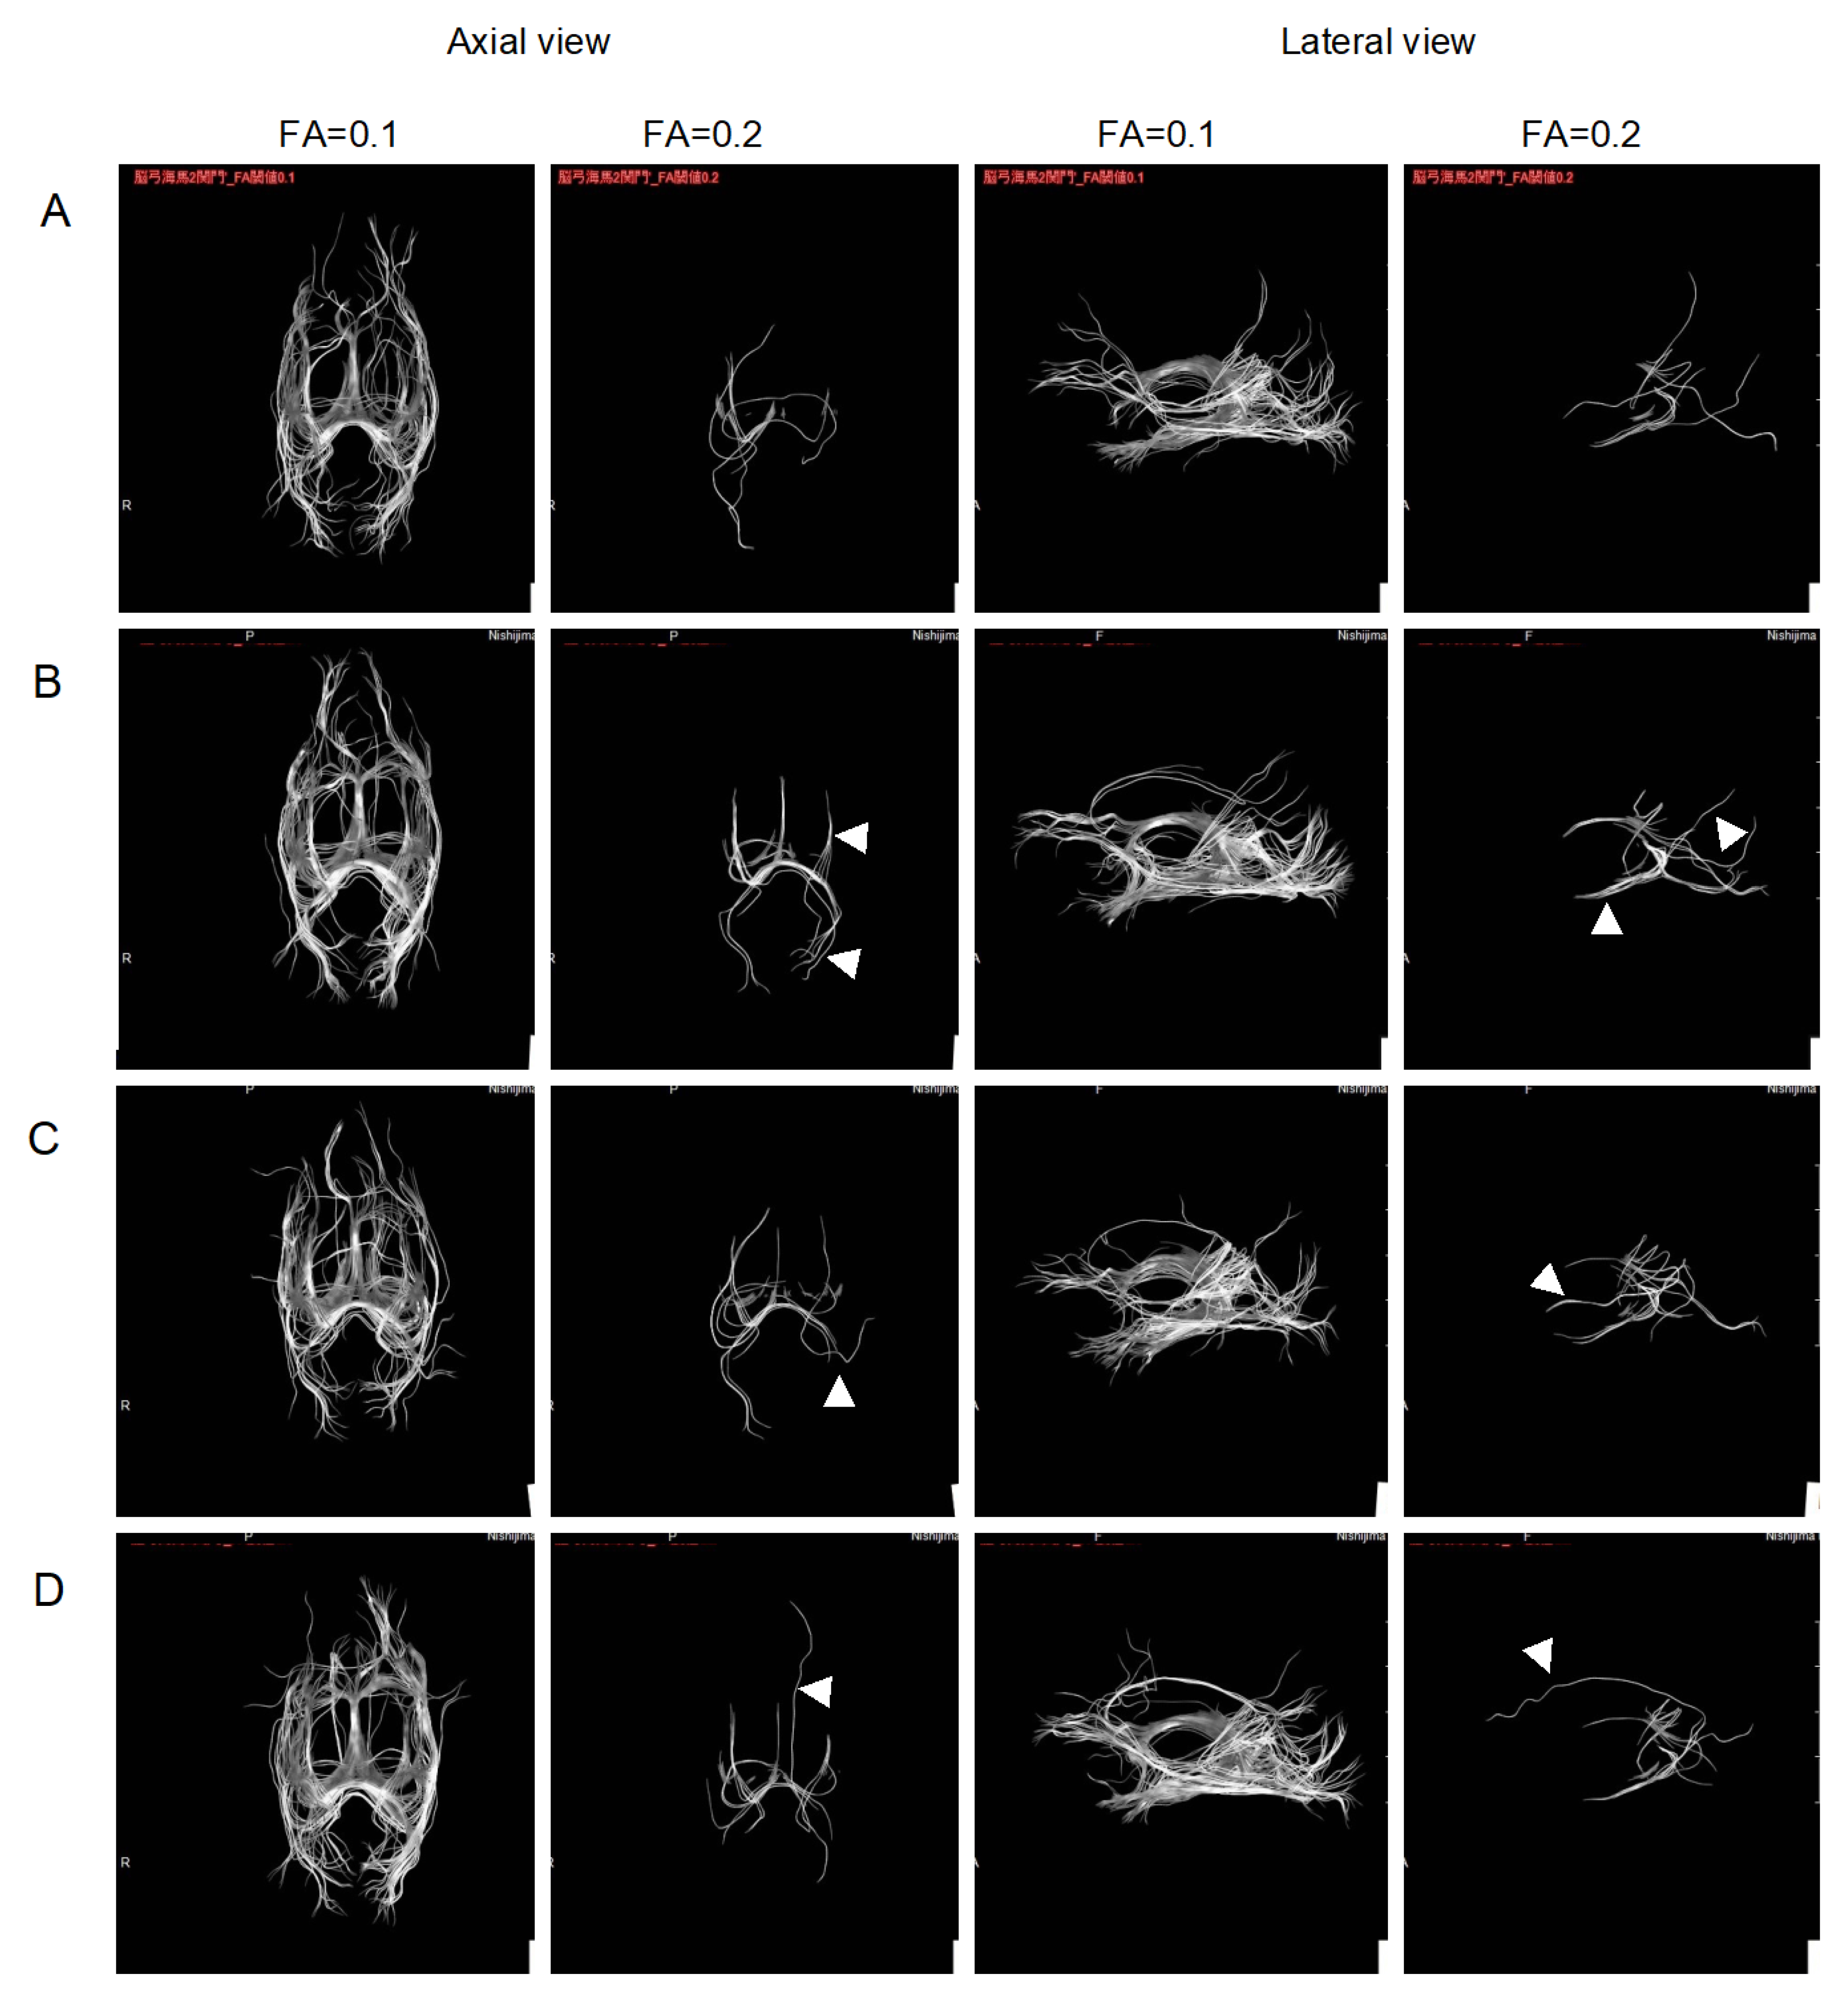

2.2. Improvement of Neurons by H2 Inhalation as Assessed by Diffusion Tensor Imaging

4.6. Measurement of the Integrity of Neurons by Diffusion Tensor Imaging